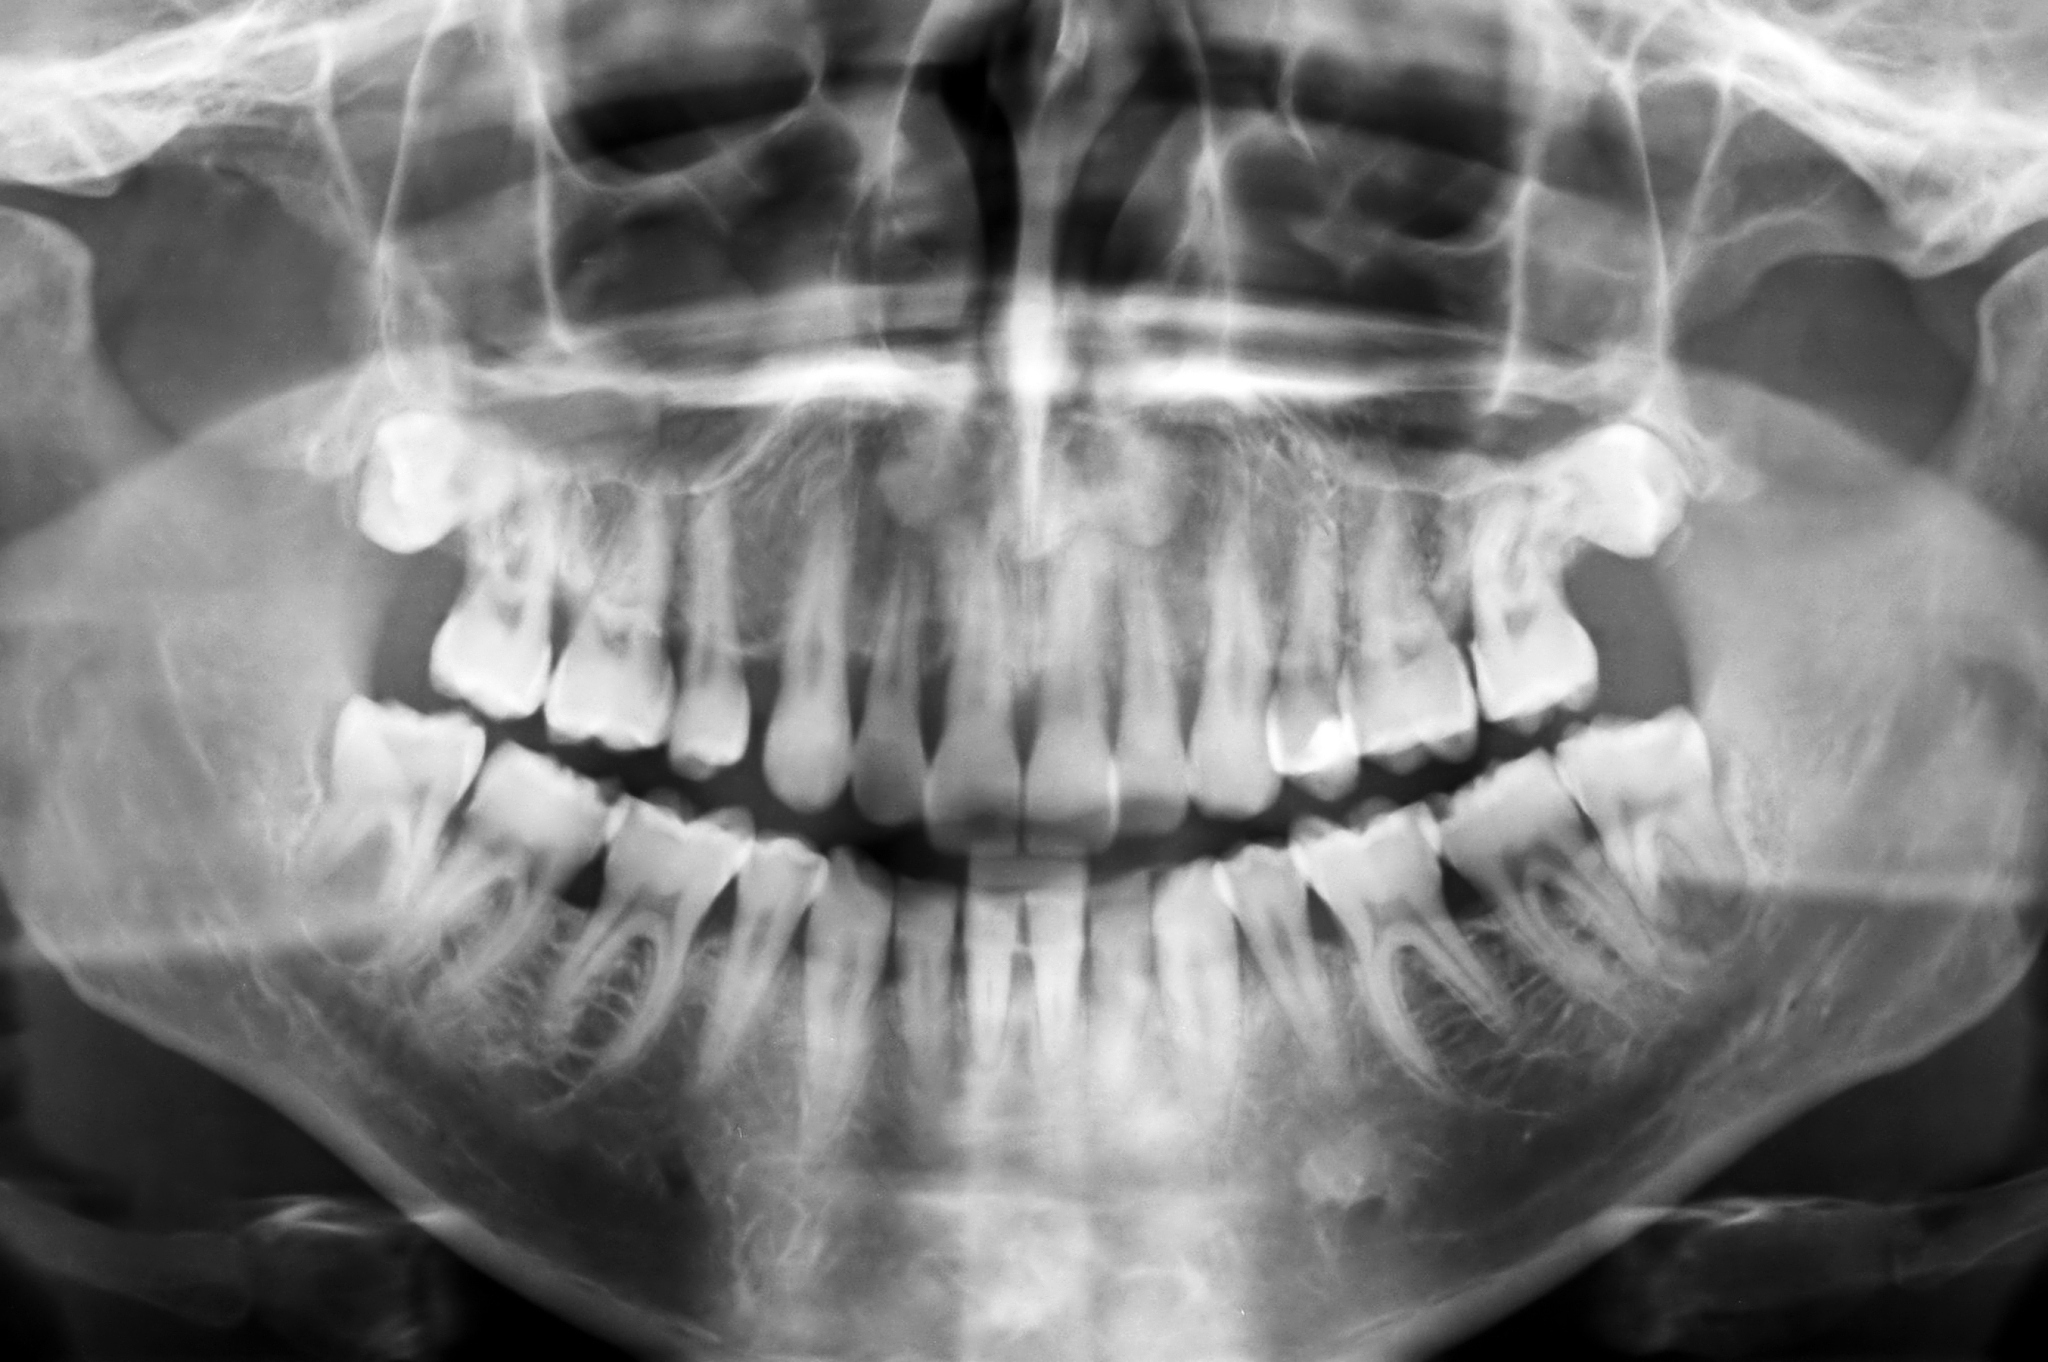

医学专业是该校的重点专业之一,包括临床医学、口腔医学、医学影像等。临床医学专业是学校的核心专业,培养具备扎实的医学理论知识和丰富的实践经验的医学人才。口腔医学专业则是近年来的热门专业之一,学生将接受口腔疾病的诊疗、口腔美容等方面的培训。

口腔医学专业则是近年来的热门专业之一,学生将接受口腔疾病的诊疗、口腔美容等方面的培训。该专业的毕业生可以在口腔医院、口腔美容诊所等单位就业,也可以自主创业,开办自己的口腔医疗机构。